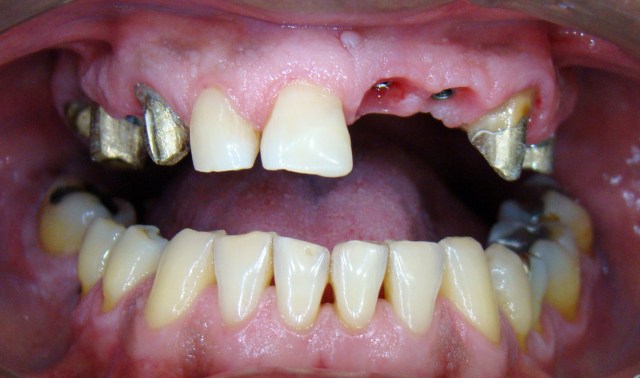

Neste caso o paciente apresentava algumas ausências dentárias e algumas coroas meta...